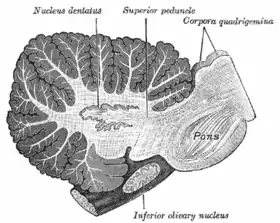

Sagittal section through right cerebellar hemisphere. The right olive, "inferior olivary nucleus", has also been cut sagittally – from front to back. (Dentate nucleus, "nucleus dentatus", labeled at top.) | |